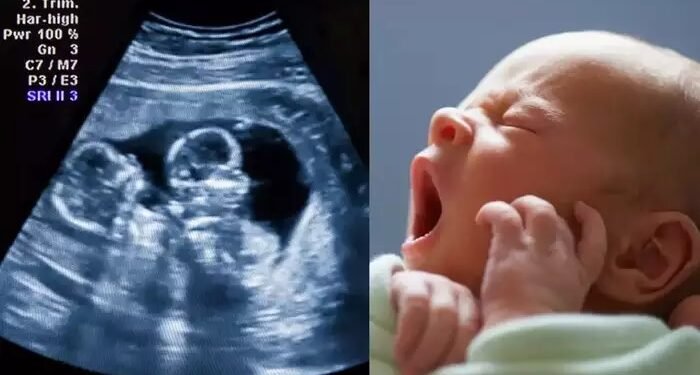

अल्ट्रासाऊंडमध्ये दोन बाळं दिसत असताना प्रसुतीनंतर महिलेच्या कुटुंबाकडे केवळ एकच बाळ देण्यात आलं. दुसरं बाळ कुठे आहे असा प्रश्न मग कुटुंबाकडून विचारण्यात आला.

त्तर प्रदेशच्या बस्तीमध्ये धक्कादायक घटना घडली आहे. जिल्हा महिला रुग्णालयाच्या ऑपरेशन थिएटरमधून बाळ गायब झाल्याचा प्रकार समोर आला आहे. नवजात बाळ चोरीला गेल्याचा आरोप प्रसुती झालेल्या महिलेच्या कुटुंबियांनी केला. अल्ट्रासाऊंड रिपोर्टमध्ये दोन बाळं दिसत होती. पण प्रसुतीनंतर आम्हाला केवळ एकच बाळ देण्यात आलं, असा दावा कुटुंबियांनी केला.

या प्रकरणाची तक्रार प्रसूत झालेल्या महिलेचे पती रमेश कुमार यांनी सीएमएसकडे केली. रमेश कुमार यांनी रुग्णालय व्यवस्थापनावर गंभीर आरोप केले आहेत. घटना नगर पोलीस ठाण्याच्या हद्दीत येणाऱ्या दुबखरा गावात घडली आहे. नुकत्याच बाळंत झालेल्या रेखा यांचे पती रमेश कुमार यांचे पती सीएमएसकडे तक्रार दिली आहे. त्यात त्यांनी घटनाक्रमाचा उल्लेख केला आहे. २९ डिसेंबरच्या दुपारी तीन वाजता मी पत्नीला रुग्णालयात दाखल केलं. संध्याकाळी पाचच्या सुमारास शस्त्रक्रिया झाली. त्यानंतर आमच्या हाती एक बाळ देण्यात आलं. पण अल्ट्रासाऊंडमध्ये पत्नीच्या गर्भात दोन बाळं दिसत होती, असं रमेश कुमार यांनी तक्रारीत म्हटलं आहे.

प्रसुती झालेल्या महिलेच्या पतीनं या प्रकरणी तक्रार दिल्याची माहिती सीएमएस प्रदिप कुमार श्रीवास्तव यांनी दिली. अल्ट्रासाऊंडमध्ये दोन बाळं दिसत होती. पण आम्हाला ऑपरेशननंतर केवळ एकच बाळ देण्यात आलं, असं त्यांनी तक्रारीत नमूद केलं आहे. एक बाळ कुठे गेलं याचा शोध घेण्यासाठी आम्ही चौकशी सुरू केली आहे. लवकरच कारवाई केली जाईल, असं श्रीवास्तव म्हणाले.